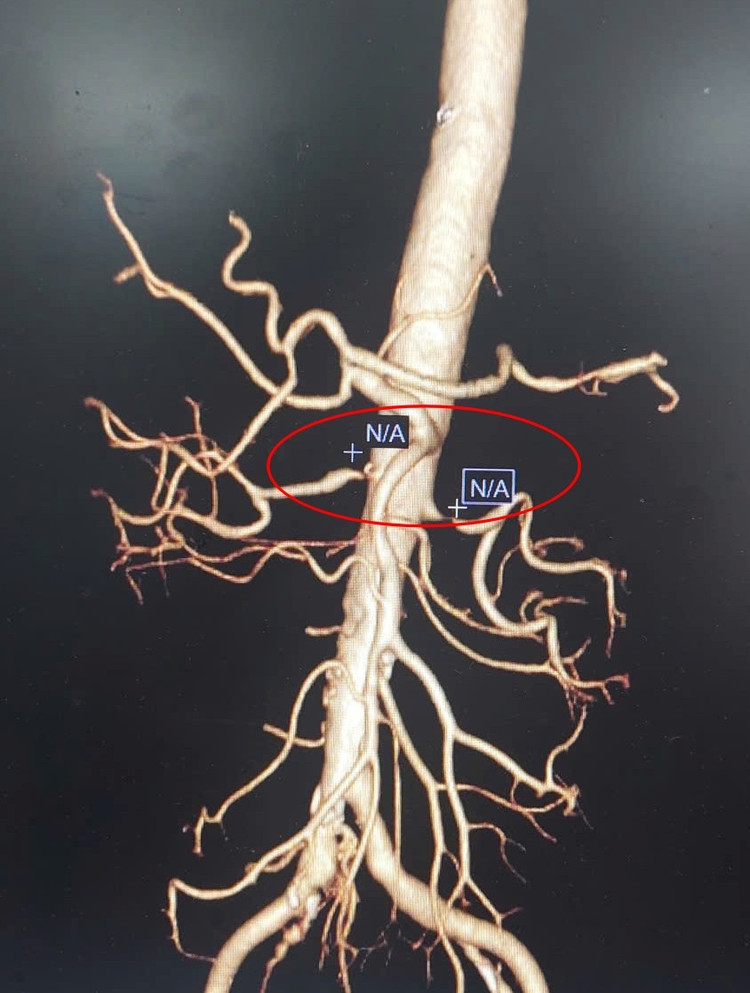

Hình ảnh CLVT dựng hình 3D động mạch thận hai bên hẹp tắc nặng - Ảnh BVCC

Bệnh nhân được chỉ định siêu âm mạch thận và chụp cắt lớp vi tính mạch máu để tầm soát, kết quả cho thấy hình ảnh hẹp nặng gốc động mạch thận hai bên, mức độ hẹp trên 80%.

Các bác sĩ đánh giá đây chính là nguyên nhân khiến việc điều trị bằng thuốc không mang lại hiệu quả, dẫn đến tình trạng tăng huyết áp kháng trị. Sau khi hội chẩn, kíp bác sĩ chỉ định tiến hành can thiệp nong và đặt stent động mạch thận cho bệnh nhân để xử trí triệt để.